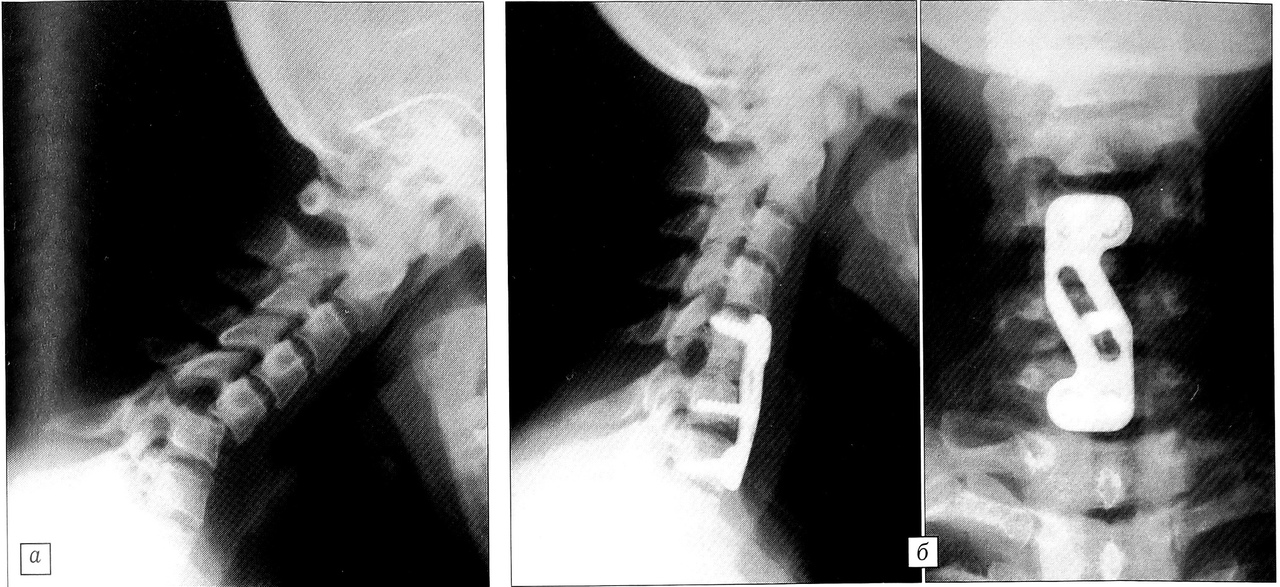

Рис. 2. Больной 49 лет: a — переломовывих С5 позвонка; б — проведено двухэтапное оперативное лечение: резекция суставных отростков на уровне С5~6 и затем открытое вправление позвонка пластиной «Orion» в сочетании с передним спондилодезом трансплантатом из крыла подвздошной кости

Из 28 больных с повреждениями нижнешейного отдела позвоночника гало-аппарат был применен у 13. У 14 больных с переломовывихами проведено оперативное лечение с фиксацией пластиной «Orion». В 11 случаях выполнена одноэтапная операция передним доступом с открытым устранением дислокации позвонков, дискэктомией или резекцией тел позвонков, аутопластикой дефекта трансплантатом из крыла подвздошной кости и фиксацией пластиной. У 4 больных с застарелыми сцепившимися переломовывихами предпринято двухэтапное оперативное лечение: сначала из заднего доступа произведены резекция суставных отростков и мобилизация задних элементов, а через 10-12 дней из переднего доступа — открытое устранение вывиха, передний спондилодез аутотрансплантатом и пластиной «Orion» (рис. 2). При вправлении позвонков использовался элеватор либо дистрактор из набора CD. Один больной с переломовывихом С7 позвонка был оперирован задним доступом с использованием системы «Axis», винты проводились в суставные отростки Т1, С7, С6 под контролем ЭОП.